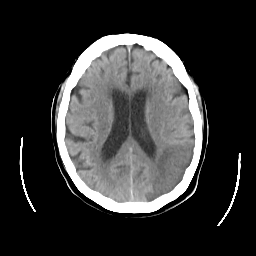

CT Study #2 -- Slice #17